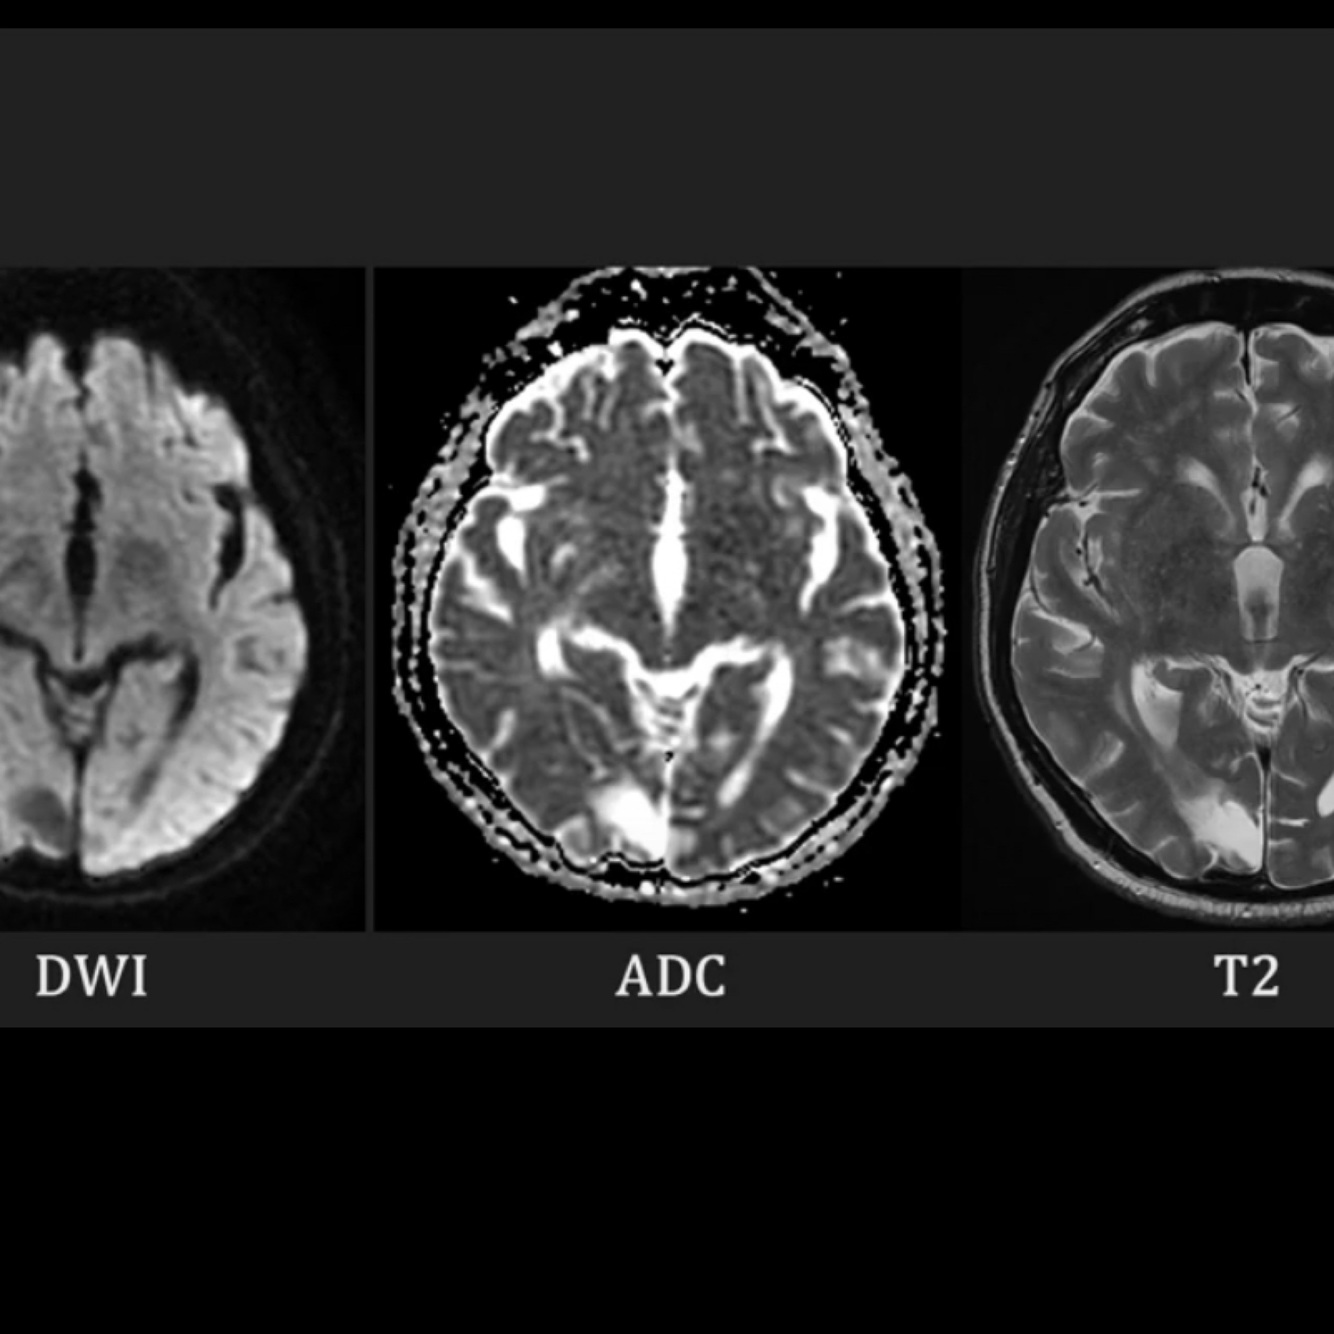

Acute infarct on MRI (DWI ADC T2)

A

DWI high attenuation

ADC low attenuation

T2 high attenuation